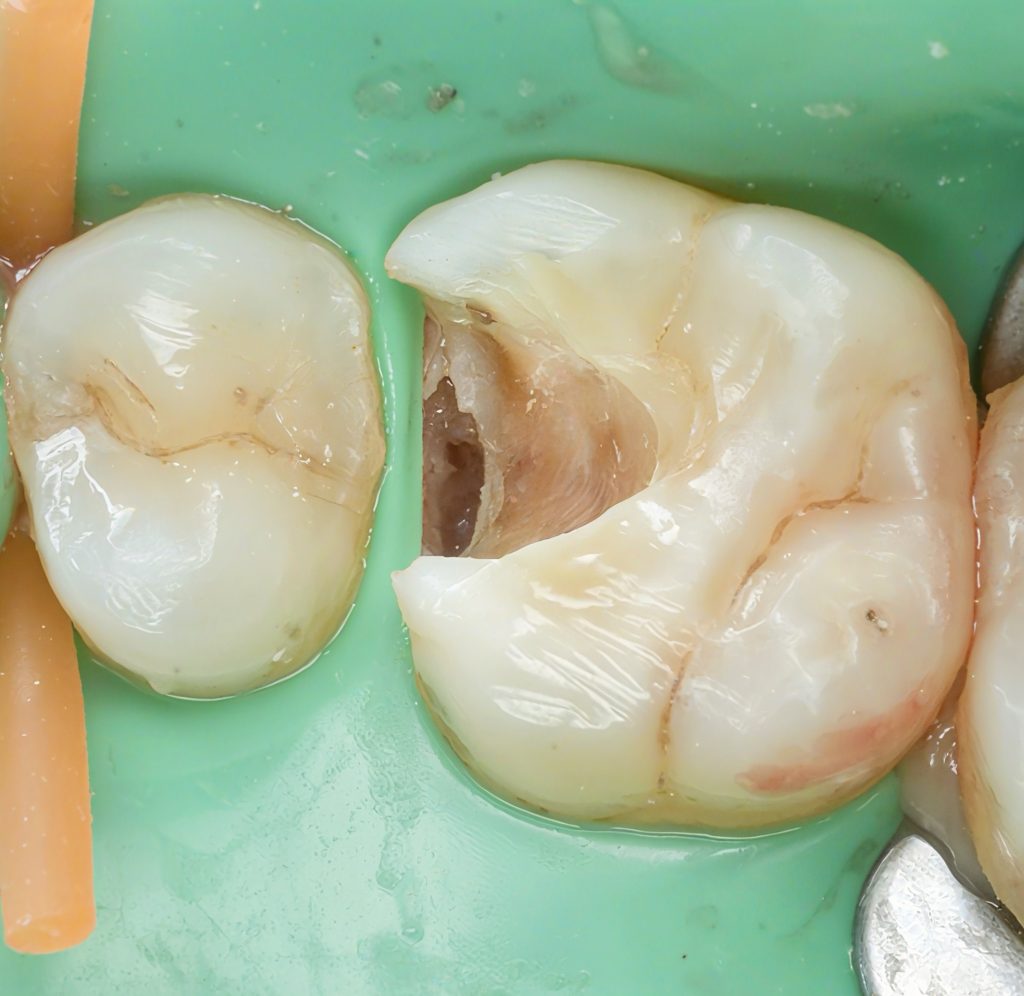

A lower posterior tooth presented with an incipient proximal lesion visible clinically and radiographically. The goal was simple: treat early disease with minimal preparation, preserve enamel, and rebuild a tight contact with a controlled adhesive workflow.

The tooth was isolated with a heavy-weight rubber dam. Caries was removed selectively until a clean enamel–dentin interface was reached. No extension for convenience. No unnecessary sacrifice of structure.

Only undermined enamel and infected dentin were removed—nothing more.